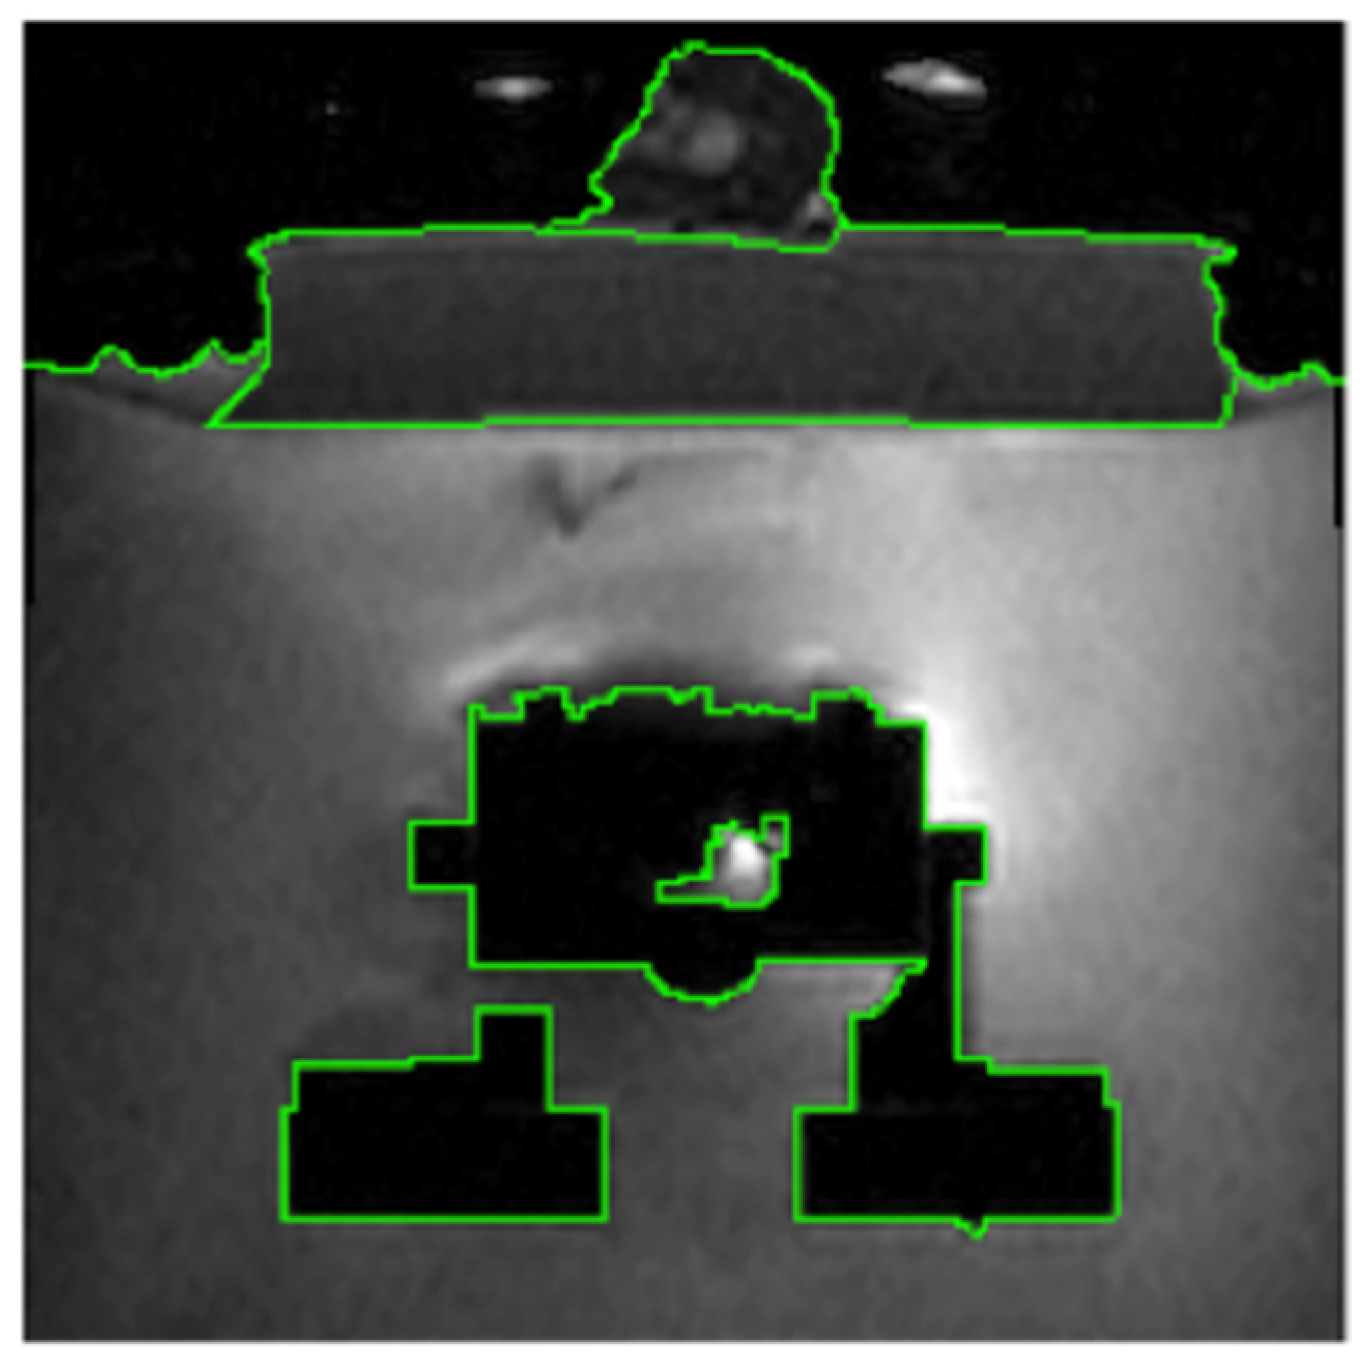

Segmentation of Transducer and Water Regions

3.3. Segmentation of the Transducer Region (TLSM Approach)